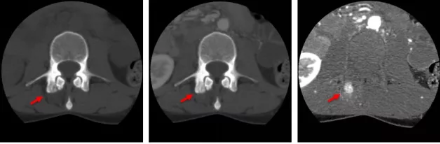

3.定量,高效與標(biāo)準(zhǔn)化的CT影像學(xué)新方案——AI柔性減影成像

通過AI感知掃描及AI柔性配準(zhǔn)的前處理,開拓者Ai-640CT即可進(jìn)行AI柔性減影成像。通過對兩期或多期數(shù)據(jù)的綜合比對分析,就可以在常規(guī)掃描中挖掘得到更多的圖像信息,并得到定量的分析結(jié)果,為臨床診斷提供更準(zhǔn)確的影像證據(jù)。

骨智能柔性減影成像功能發(fā)現(xiàn)隱匿骨占位病灶